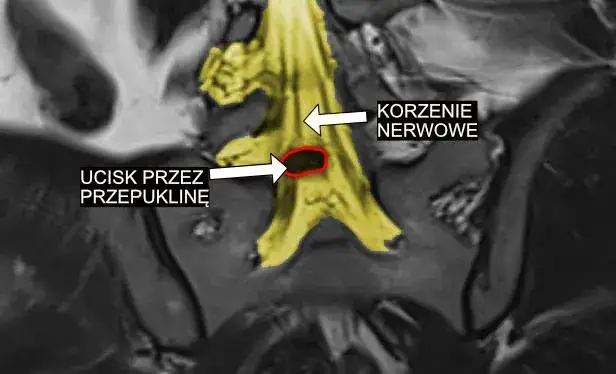

Korzenie nerwowe to struktury, które łączą nerwy obwodowe z rdzeniem kręgowym. Są one kluczowe dla przekazywania sygnałów między mózgiem a resztą ciała. Zaburzenia korzeni nerwowych mogą prowadzić do problemów z czuciem i ruchem w określonych obszarach ciała.

- Radikulopatia - ucisk korzenia nerwowego

Korzenie nerwowe to struktury, które wychodzą bezpośrednio z rdzenia kręgowego. Każdy korzeń nerwowy składa się z włókien czuciowych i ruchowych. Tworzą one most między ośrodkowym a obwodowym układem nerwowym.

Specyficzne objawy zależą od lokalizacji uszkodzenia. Na przykład, problemy z korzeniami nerwowymi w odcinku lędźwiowym mogą powodować ból promieniujący do nóg. Z kolei zaburzenia splotu ramiennego mogą prowadzić do osłabienia i bólu w ramieniu i dłoni. Dokładna diagnoza wymaga szczegółowego badania neurologicznego.

W celu potwierdzenia diagnozy często konieczne są dodatkowe badania. Mogą to być badania obrazowe, takie jak rezonans magnetyczny czy tomografia komputerowa. Czasami wykonuje się również badania elektrofizjologiczne, jak elektromiografia (EMG) czy badanie przewodnictwa nerwowego. Te testy pomagają określić dokładną lokalizację i stopień uszkodzenia nerwów.